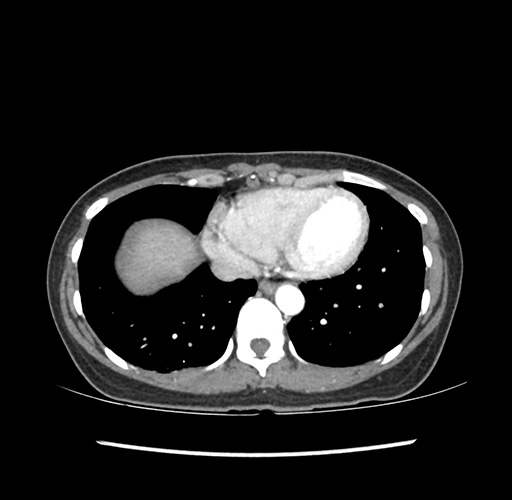

Imaging Analysis

Look through the patient's CT scan to identify any areas of concern for the necessary procedure.

Based on your CT findings, which issue(s) would give reason for "planned slowing down moment(s)" in this case?